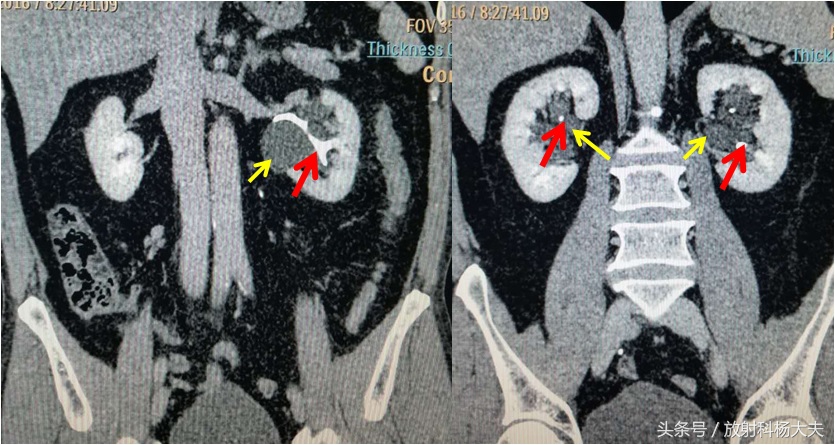

注射对比剂后,可以看到红箭为充盈对比剂的正常肾盂。黄箭为肾盂旁囊肿。